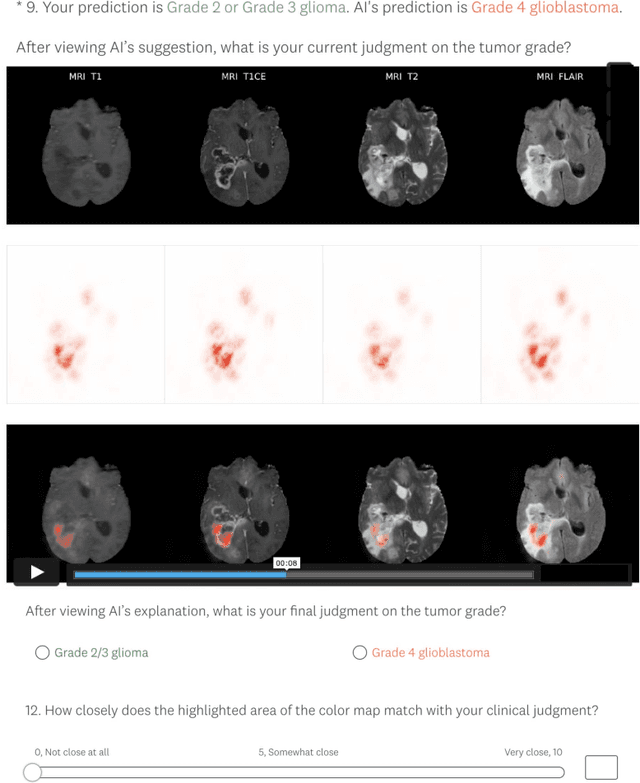

Abstract:Being able to explain the prediction to clinical end-users is a necessity to leverage the power of artificial intelligence (AI) models for clinical decision support. For medical images, a feature attribution map, or heatmap, is the most common form of explanation that highlights important features for AI models' prediction. However, it is unknown how well heatmaps perform on explaining decisions on multi-modal medical images, where each image modality or channel visualizes distinct clinical information of the same underlying biomedical phenomenon. Understanding such modality-dependent features is essential for clinical users' interpretation of AI decisions. To tackle this clinically important but technically ignored problem, we propose the modality-specific feature importance (MSFI) metric. It encodes clinical image and explanation interpretation patterns of modality prioritization and modality-specific feature localization. We conduct a clinical requirement-grounded, systematic evaluation using computational methods and a clinician user study. Results show that the examined 16 heatmap algorithms failed to fulfill clinical requirements to correctly indicate AI model decision process or decision quality. The evaluation and MSFI metric can guide the design and selection of XAI algorithms to meet clinical requirements on multi-modal explanation.

Abstract:Explainable artificial intelligence (XAI) is essential for enabling clinical users to get informed decision support from AI and comply with evidence-based medical practice. Applying XAI in clinical settings requires proper evaluation criteria to ensure the explanation technique is both technically sound and clinically useful, but specific support is lacking to achieve this goal. To bridge the research gap, we propose the Clinical XAI Guidelines that consist of five criteria a clinical XAI needs to be optimized for. The guidelines recommend choosing an explanation form based on Guideline 1 (G1) Understandability and G2 Clinical relevance. For the chosen explanation form, its specific XAI technique should be optimized for G3 Truthfulness, G4 Informative plausibility, and G5 Computational efficiency. Following the guidelines, we conducted a systematic evaluation on a novel problem of multi-modal medical image explanation with two clinical tasks, and proposed new evaluation metrics accordingly. The evaluated 16 commonly-used heatmap XAI techniques were not suitable for clinical use due to their failure in \textbf{G3} and \textbf{G4}. Our evaluation demonstrated the use of Clinical XAI Guidelines to support the design and evaluation for clinically viable XAI.

Abstract:Being able to explain the prediction to clinical end-users is a necessity to leverage the power of AI models for clinical decision support. For medical images, saliency maps are the most common form of explanation. The maps highlight important features for AI model's prediction. Although many saliency map methods have been proposed, it is unknown how well they perform on explaining decisions on multi-modal medical images, where each modality/channel carries distinct clinical meanings of the same underlying biomedical phenomenon. Understanding such modality-dependent features is essential for clinical users' interpretation of AI decisions. To tackle this clinically important but technically ignored problem, we propose the MSFI (Modality-Specific Feature Importance) metric to examine whether saliency maps can highlight modality-specific important features. MSFI encodes the clinical requirements on modality prioritization and modality-specific feature localization. Our evaluations on 16 commonly used saliency map methods, including a clinician user study, show that although most saliency map methods captured modality importance information in general, most of them failed to highlight modality-specific important features consistently and precisely. The evaluation results guide the choices of saliency map methods and provide insights to propose new ones targeting clinical applications.